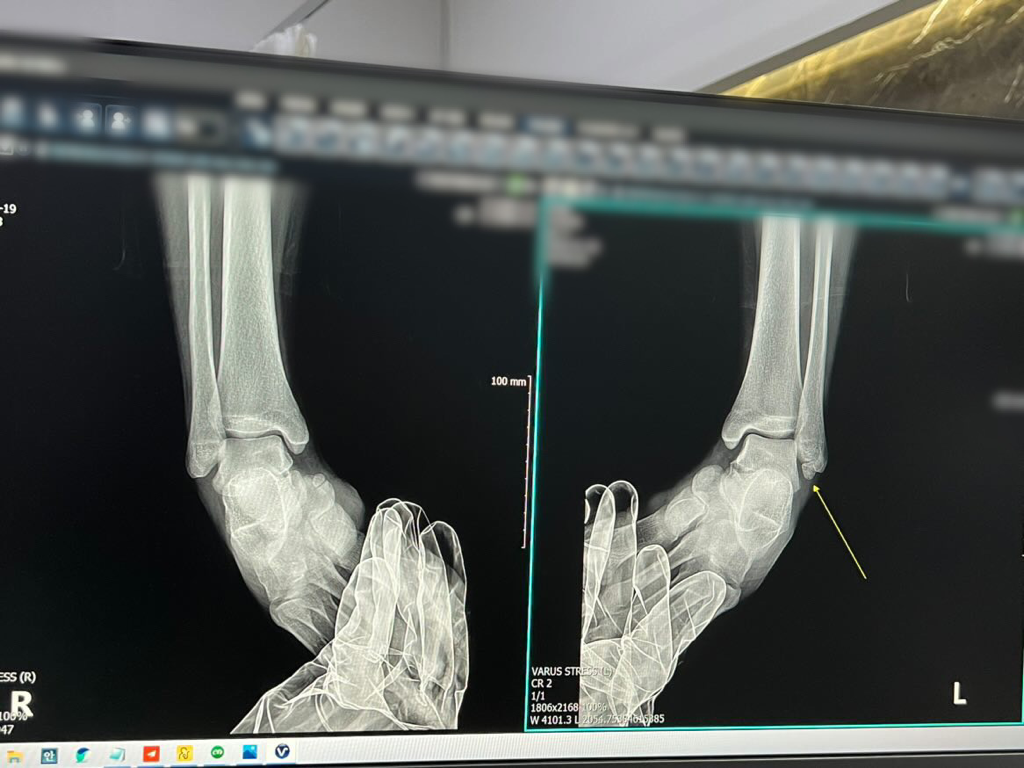

발목에 뼛조각 수술해야하나요?

두번째, 세번째 병원에서는 발목에 뼛조각 있는 건 알고 계시죠? 하시며 언급 정도만 하셨습니다

네번째 병원에서는 발목에 뼛조각이 인대를 잡고 떨어져서 수술을 고려해보아야 하는데 아직 수술할 정도는 아니라 지켜보되 조심하라고 말씀해주셔서 신경을 쓰고 지내고 있었습니다

오늘 발을 헛디뎌 발목이 아파 다른 병원에 갔을 때는 뼛조각이 있긴한데 크게 신경 안써도 된다고 하셔서 어느 분 말씀이 맞는건지 잘 모르겠습니다ㅜㅜ

네번째 선생님이 찍어두라고 하셨던 사진첨부합니다

• 1번 째 사진

발목뼛조각이 있다고 하더라도 특별히 문제가 되지 않으면 우선은 경과를 관찰하게 되지만 발목뼛조각이 있으면서 지속적으로 관절 내부를 자극하게 되면 만성적인 염좌나 통증 등의 문제를 유발할 수 있습니다.

이 경우 수술적 치료의 대상이 되며, 발목뼛조각을 제거하는 수술 외에도 인대나 연골 등의 손상 여부도 파악해서 추가적인 치료를 진행하게 될 수도 있습니다.